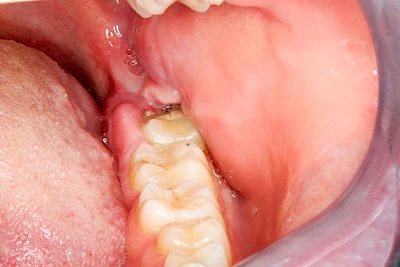

Sonderform: Schlupfwinkelinfektion

Im Laufe der menschlichen Entwicklung haben sich die Kiefer aufgrund unserer Nahrungsumstellung rückgebildet. Die Weisheitszähne haben daher oft keinen Platz mehr. Bei ca. 30 % der Menschen sind diese Zähne schon gar nicht mehr angelegt. Zum Teil liegen die Zähne versteckt (retiniert) im Kiefer und sind nicht sichtbar. Hin und wieder brechen die Zähne zwar durch die Schleimhaut, aber nicht vollständig – es handelt sich um einen erschwerten Zahndurchbruch (dentitio difficilis). Dann sind die Zähne noch teilweise bedeckt von einer "Schleimhautkapuze". Gehen hier Speisereste und Bakterien unter die Schleimhautkapuze kann sich eine sogenannte Schlupfwinkelinfektion bilden. Diese Entzündungen treten spontan auf, sind häufig sehr schmerzhaft und die Mundöffnung ist eingeschränkt. Hier ist umgehend der Zahnarzt zu kontaktieren.